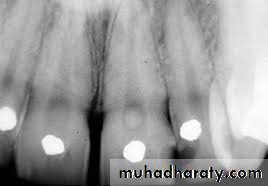

Denticles/pulp stones. These are usually seen in pulp chamber.

According to location:•Free

• Embedded

• Attached

•True

• False

True denticles: It is composed of dentin formed from detached odontoblasts or fragments of Hertwig’s enamel root sheath which stimulate and undifferentiated cells to assume dentinoblastic activity.

False denticles: Here degenerated tissue structures act as nidus for deposition of concentric layers of calcified tissues.